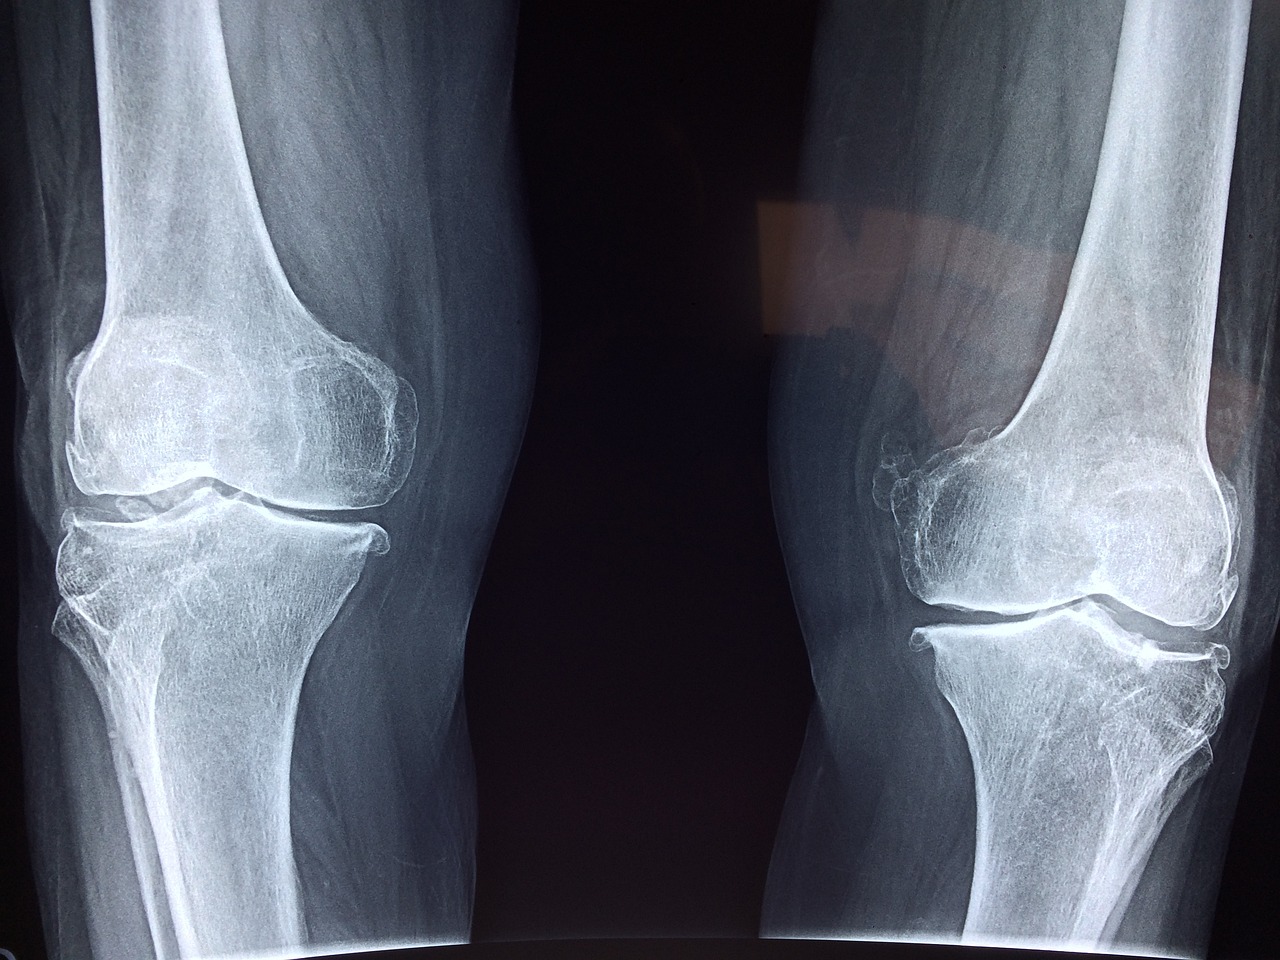

저는 처음 가족이 질병 판정을 받았을 때, 산정특례 대상이 될 수 있을지 굉장히 막막했습니다. 다행히 병원에서 안내를 받아 산정특례 대상 여부를 바로 확인할 수 있었어요. 산정특례 대상은 암, 희귀난치성질환, 중증질환(뇌혈관, 심장, 중증화상 등), 결핵, 중증소아질환, 1형당뇨 등이 해당합니다. 대상자 확인은 국민건강보험공단 홈페이지에서 가능하며, 병원 원무과나 진단의뢰 시에도 직접 확인해줍니다. 제가 경험한 팁을 하나 드리자면, 진단서와 의료기록 사본을 미리 준비해서 건강보험공단에 문의하면 대상 여부를 빠르게 안내받을 수 있었습니다.